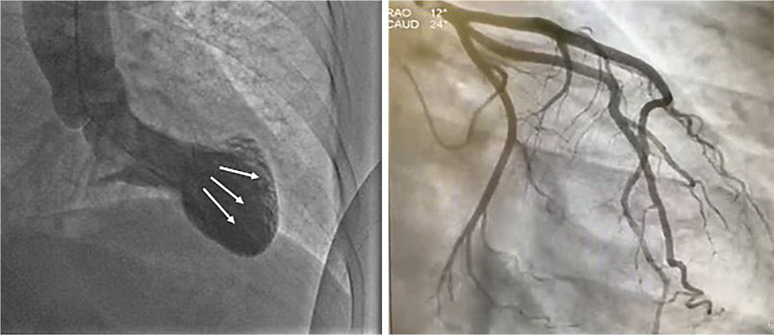

Case presentation: A smoker in their 70s with metastatic lung adenocarcinoma experienced an anaphylactic reaction during the second cycle of atezolizumab. The reaction was accompanied by chest tightness and elevated troponin T levels. Echocardiographic evaluation revealed severe dilatation of the left ventricular apex and a significantly reduced left ventricular ejection fraction. Coronary angiography excluded significant coronary stenosis but confirmed apical ballooning, consistent with the type I variant of KS. This diagnosis underscores the potential for immune-related cardiovascular events associated with ICIs to mimic acute coronary syndromes, challenging clinicians to distinguish between immune-mediated effects and primary cardiac conditions.